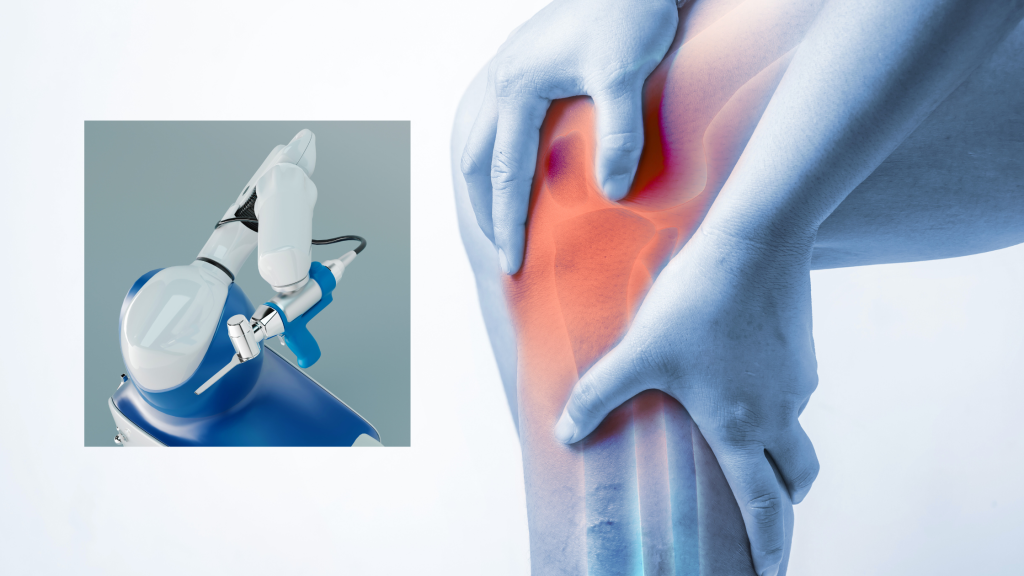

Robotic (Robot-Assisted) Knee Replacement Surgery

Robotic knee replacement is a more modern approach that incorporates advanced technology to help your surgeon perform the surgery with remarkable precision. Before your procedure, a 3D model of your knee is created using advanced imaging software.

This personalized model lets the surgeon plan exactly how to position the implant for the best possible outcome. During the surgery, the surgeon controls a robotic arm, which assists in making highly accurate cuts and preparing the bone, ensuring the artificial joint fits as perfectly as possible to your unique anatomy.